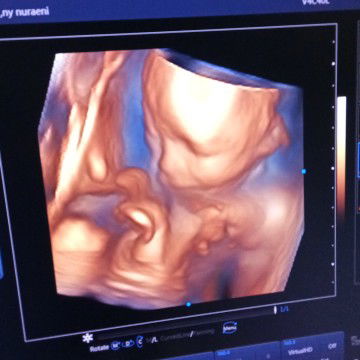

kalou USG 4D berapa yah

beda2 tergantung tempatnya. kalo klinik saya (jaksel) 305rb usg 2d+4d plus cetaknya, blm sm vitamin

klo diklinik daerah yg biasa aku usg, 150 untuk 2d, 250 untuk 4d belum termasuk vitamin ,,

kalo di daerah ku 150 Moms udah sama vitamin.. USG 4D+2D plus dapet cetak foto...

di daerahku .. 220 udah cetak foto .. tanpa vitamin

tangerang 240 usg aja kalo sma vit sampe 300 lebih

250 dijakarta timur , di klinik bunda sehat

di halobumil 220 udah dpt cetak foto dan cd

200rb (HANYA USG) + Vitamin jadi 890rb

di medan 150rb.. ada 120rb..